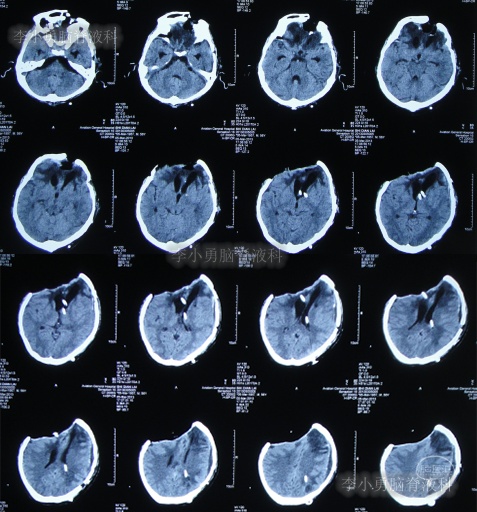

第3家医院出院后26天即2012年9月26日(开颅术后92天),因患者失语、嗜睡、吞咽障碍,第2次住入第3家医院,入院后2天即2012年9月28日,给予伤口及脑内脓肿清创缝合术+脑脊液漏修补术+右大腿取脂肪术,但术后2周即2012年10月12日,复查头颅CT提示脑积水(图-1)。

图-1:2012年10月12日头颅CT

2012年10月16日(第3家医院第2次住院20天),进行了脑室腹腔分流术(图-2)。

图-2:2012年10月16日头颅CT

脑室腹腔分流术后7天即2012年10月23日,患者突发意识丧失、双眼上翻伴头部抖动近20分钟后自行缓解,查头颅CT(图-3)后考虑为“颅内感染”。

图-3:2012年10月23日头颅CT

脑室腹腔分流术后11天即2012年10月27日,进行了脑室腹腔分流管腹腔端外置术(图-4),术中可见清亮脑脊液流出。

图-4:2012年10月27日头颅CT

治疗期间给予腰穿脑脊液检查未见细菌,但白细胞、蛋白偏高,体温仍间断升高,最高38.6度,期间查头颅CT示脑室仍有扩张(图-5)。

图-5:2012年10月30日头颅CT